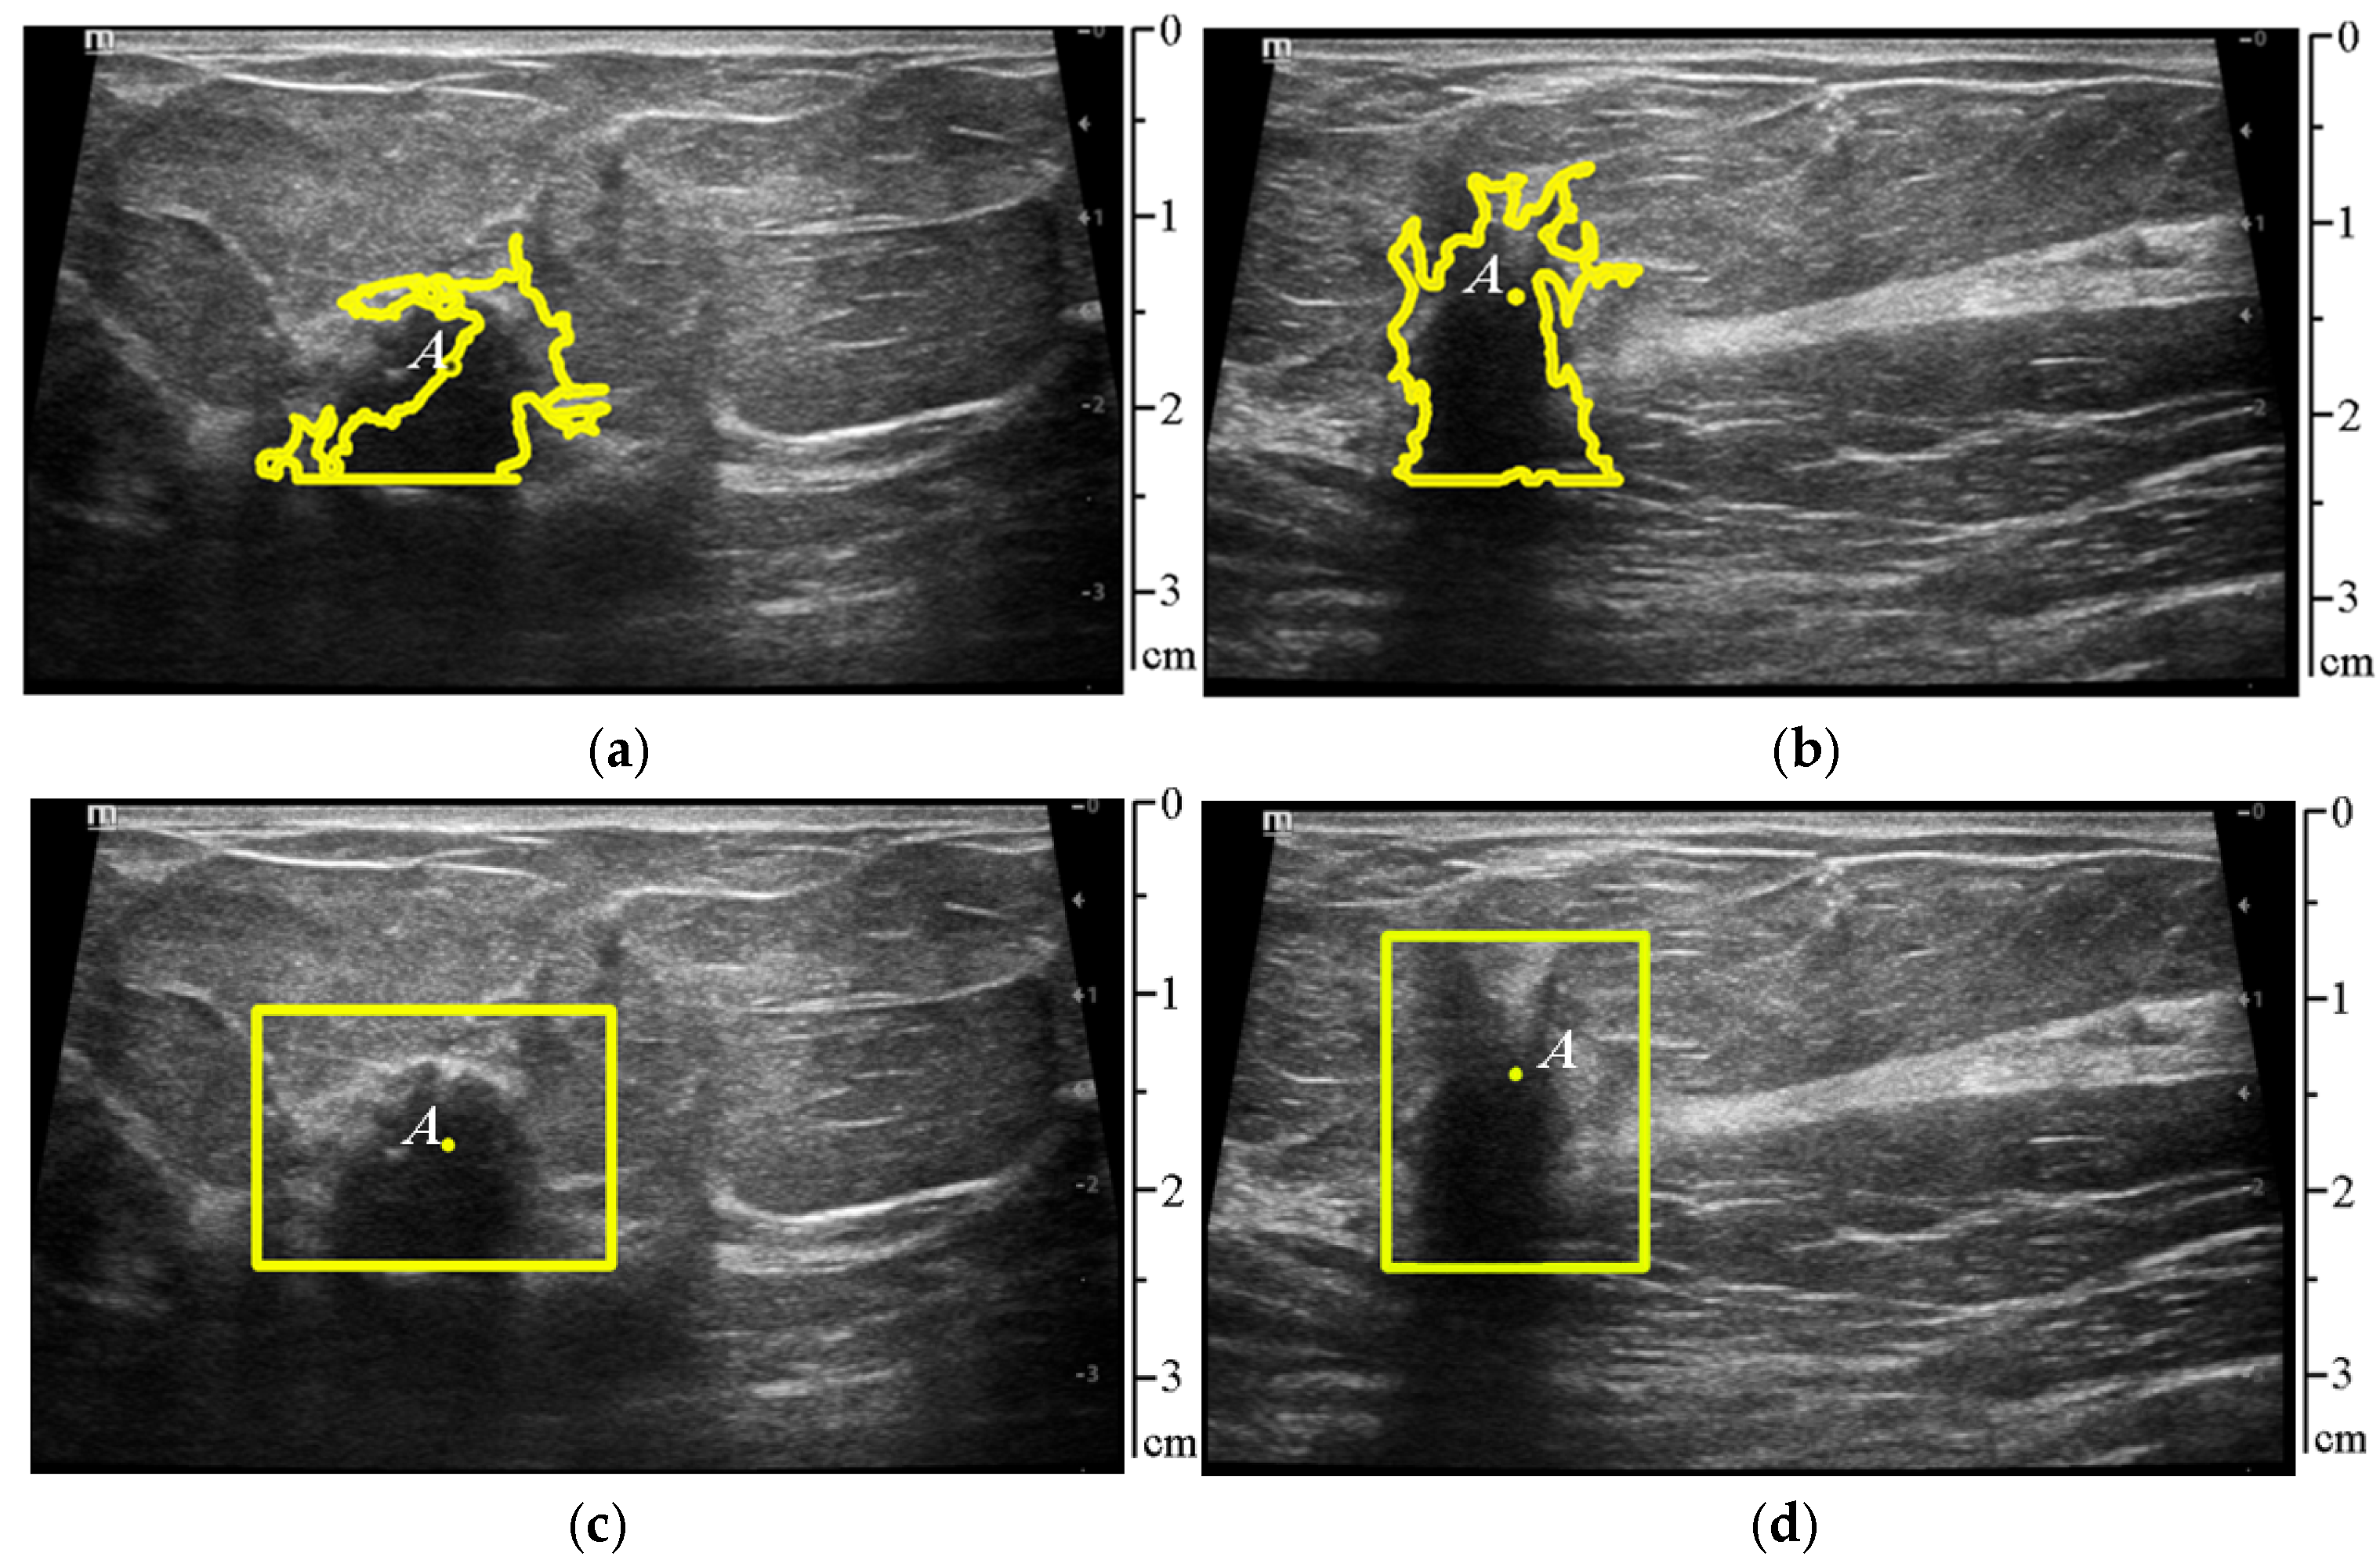

2.2.3. Segmentation of the Pathologic Lesion

3.2. Segmentation of Pathologic Lesion